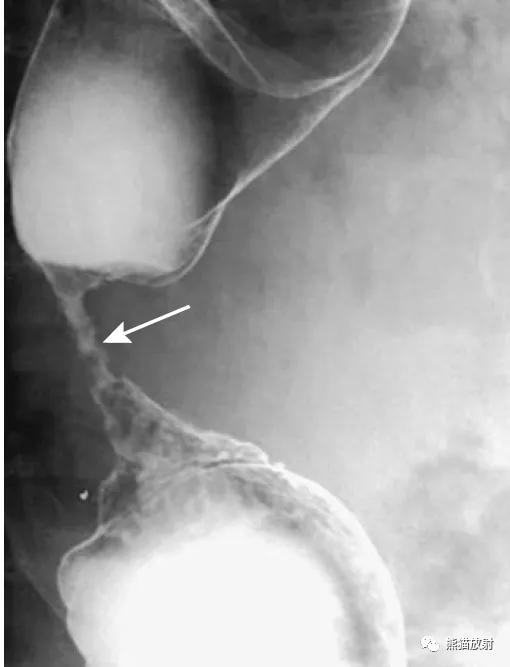

Hirschsprung病(先天性巨结肠)。钡灌肠可显示变窄的直肠(箭头)和近侧扩张的结肠。

(发病机制是远端肠管神经节细胞缺如或功能异常,使肠管处于痉挛狭窄状态,肠管通而不畅,近端肠管代偿性增大,壁增厚。)